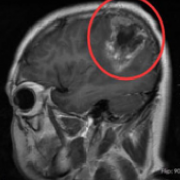

胶质瘤手术微创吗?利用激光消融胶质瘤的LITT技术或可做到

胶质瘤手术微创吗?LITT的原理是通过热选择性消融肿瘤...